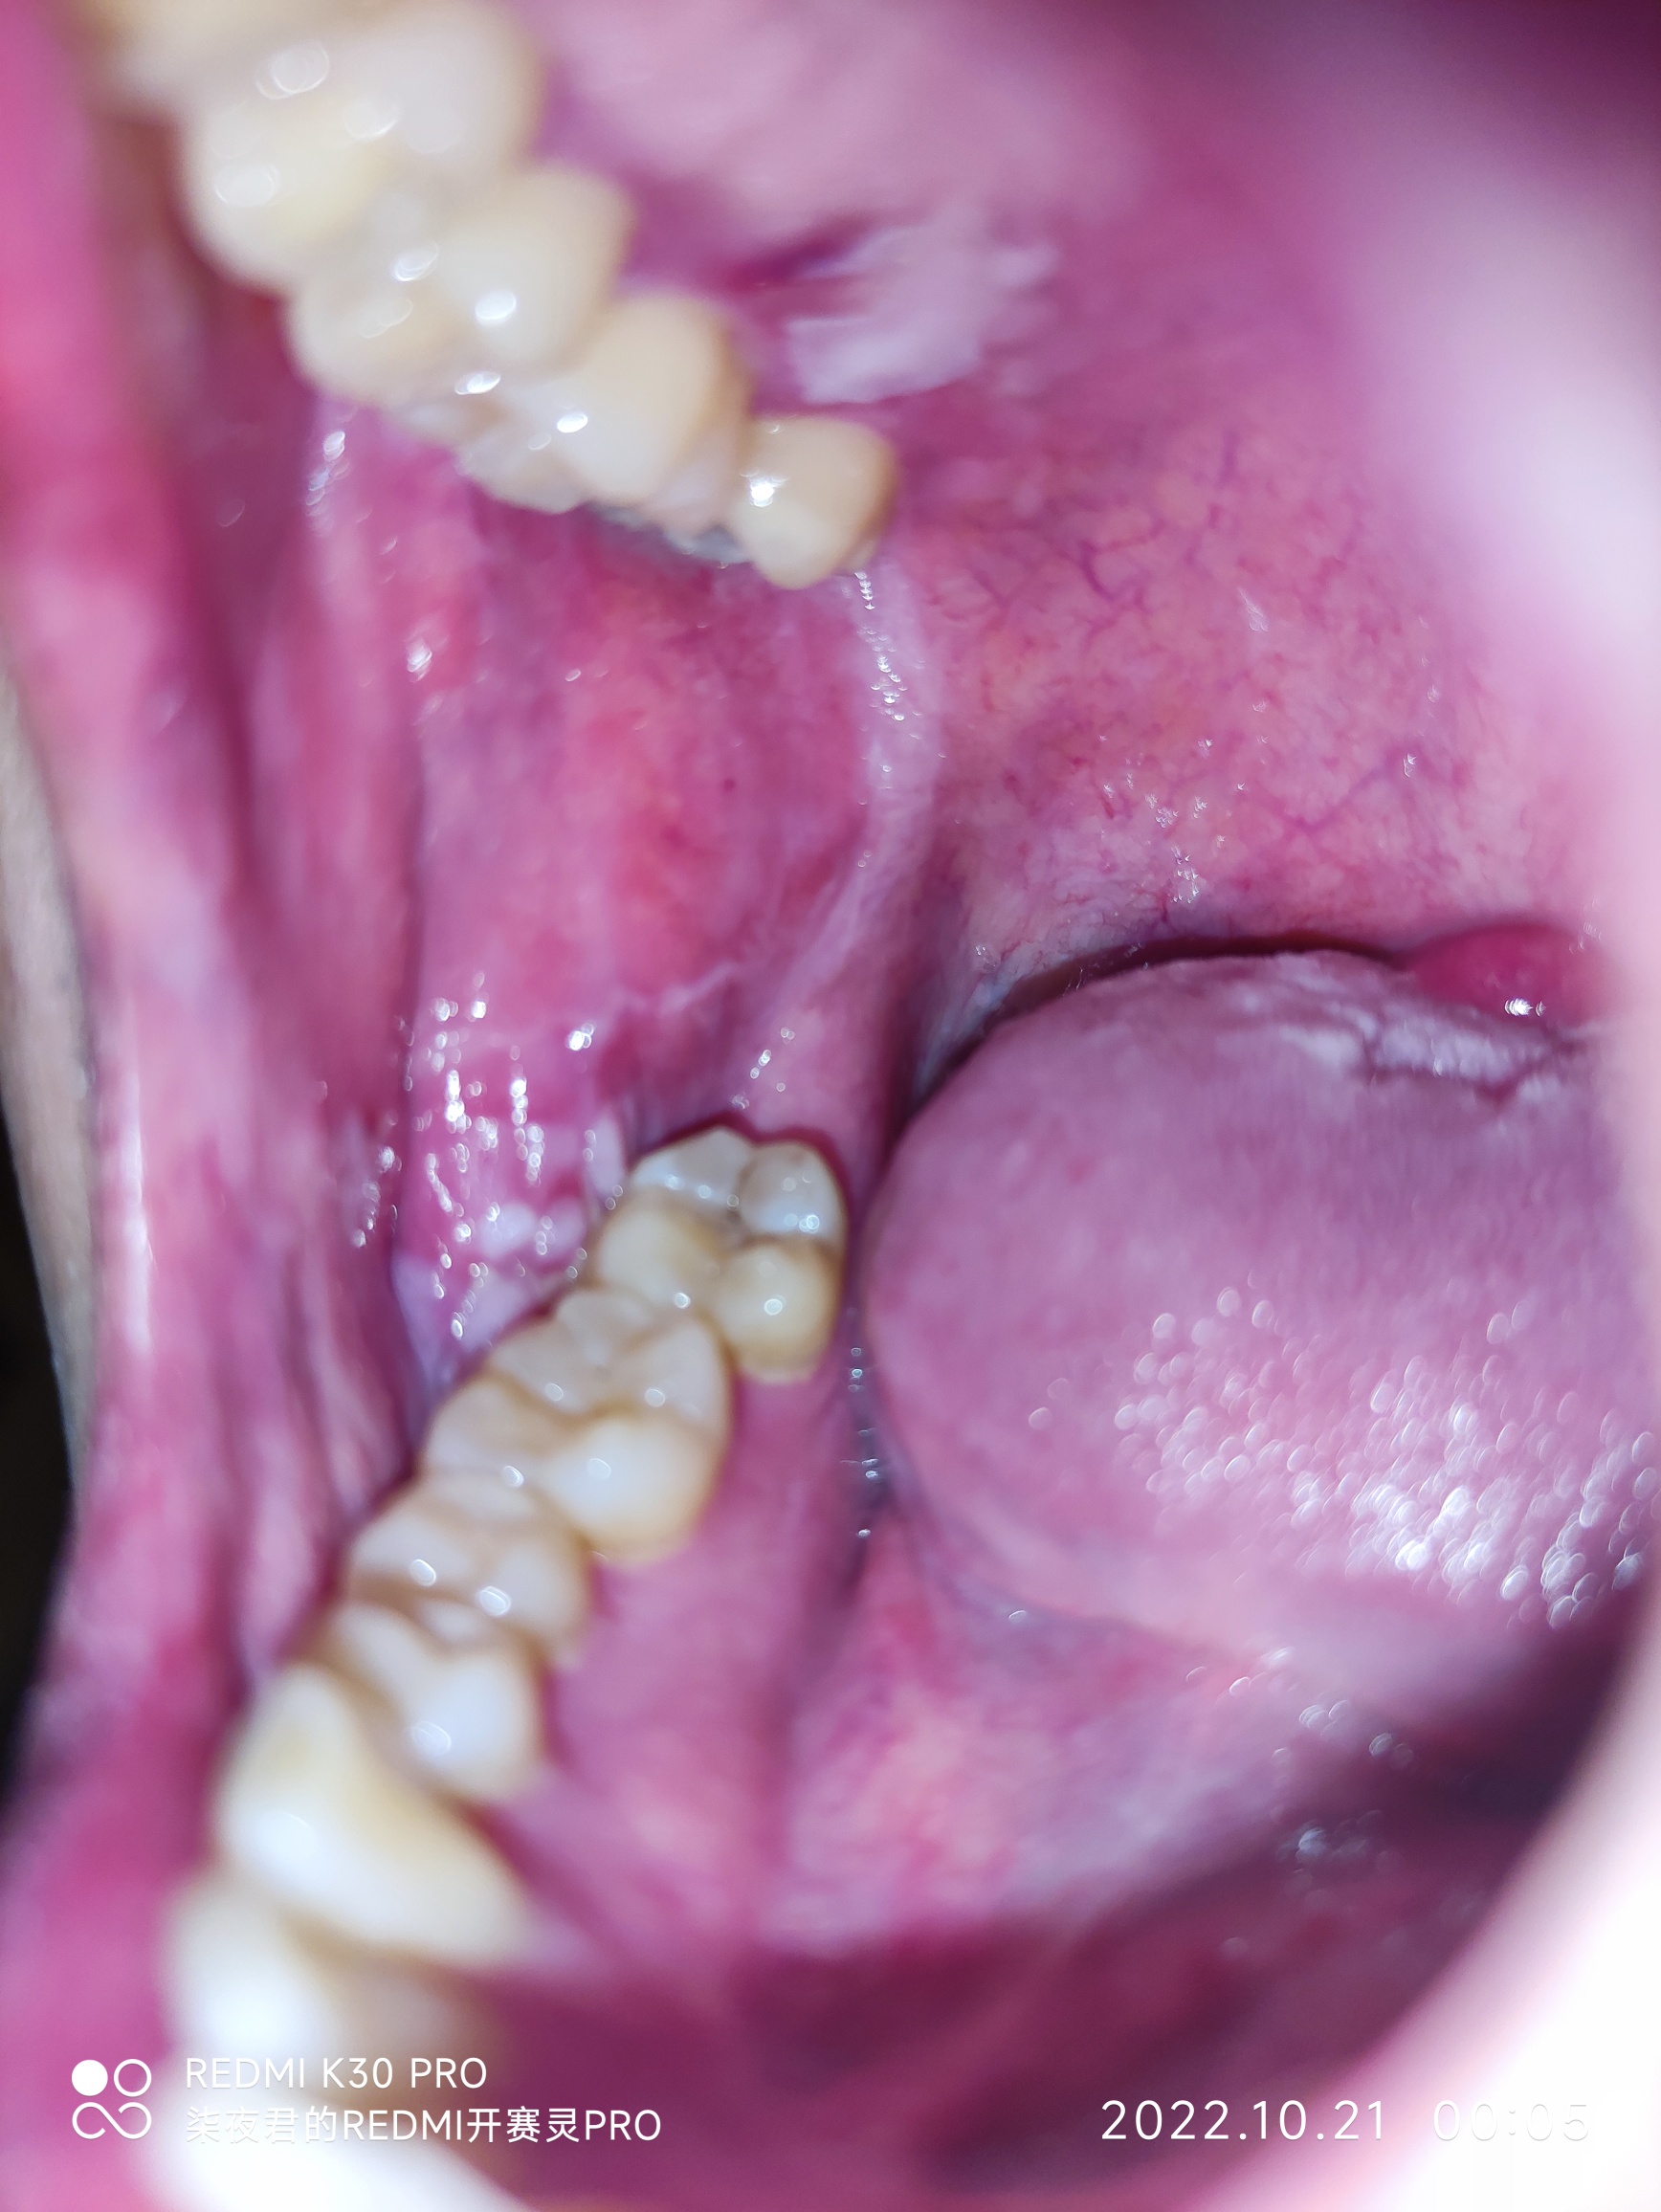

第四天,第一天和第二天是扁平的白色感觉口腔那层膜不规则破损,前面吃饭那些触碰也不疼,第三天开始突起来了,现在溃烂面积加大了,半个嘴巴都难受,酸爽,扯着头和脸颊骨都疼,再不快快好起来就要做活检了排除口腔癌病变,有这样的吗?出来聊聊,相互交流

十七,我这两天扯着半个头都不舒服,一会儿这疼,一会儿那疼,牙神经有时候还扯的疼,半个舌头和嘴巴用漱口水刺激的疼也不知道是不是正常现象,舌头上也有一些变化,舌头下面口腔黏膜上还长了几个新的黄色像水泡一样的小绿豆大小的东西,你现在口排好了没有呢?